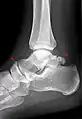

Ankle

Accessory bones at the ankle mainly include:

- Os subtibiale, with a prevalence of approximately 1%.[14] It is a secondary ossification center of the distal tibia that appears during the first year of life, and which in most people fuses with the shaft at approximately 15 years in females and approximately 17 years in males.[14]

- Os subfibulare, with a prevalence of approximately 0.2%.[15]

Os trigonum (further described below) may also be seen on an ankle X-ray.

The os trigonum or accessory talus represents a failure of fusion of the lateral tubercle of the posterior process of the talus bone. Is estimated to be present in 7–25% of adults.[17] It can be mistaken for an avulsion fracture of lateral tubercle of talus (Shepherd fracture) or a fracture of the Stieda process. In most cases, Os Trigonum will go unnoticed, but with some ankle injuries it can get trapped between the heel and ankle bones which irritates the surrounding structures, leading to Os Trigonum Syndrome.[21]